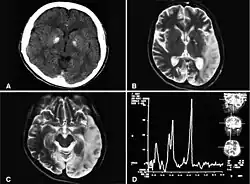

In einer Schnittbilduntersuchung des Kopfes (Computertomographie, Magnetresonanztomographie) ist ein Hirnsubstanzverlust (Atrophie) nachweisbar, sowie eine Fehlbildung der weißen Hirnsubstanz (Leukodystrophie). Hinzu kommen zahlreiche Verkalkungsherde. Daher wird die Erkrankung auch als Basalganglien-Enzephalopathie oder kalzifizierende Enzephalopathie mit intrakranialer Verkalkung und chronischer CSF-Lymphozytose bezeichnet.